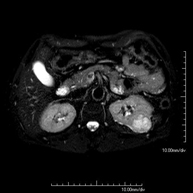

- Kidney MRI

This non-invasive diagnostic procedure uses an electromagnetic field and radio waves (from a transmitter and receiver) to acquire high-definition anatomical images of the kidneys. It is a radiation-free procedure. It is performed to study any localised injury in both kidneys. Paramagnetic contrast (gadolinium) is usually required to characterise the lesions.